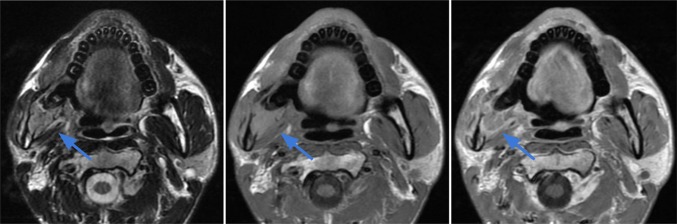

Case 8.

Alveolar soft part sarcoma (ASPS) in the right mandible of a 29-year-old male. Axial T2 (left image), T1 (middle image) and T1 post contrast (right image) demonstrate a destructive lobulated T2 hyperintense and T1 hyperintense lesion centered in the right mandibular ramus, angle and posterior body with replacement of the normal marrow signal and associated cortical bone destruction. The extraosseous soft tissue mass extends medially into the masticator space